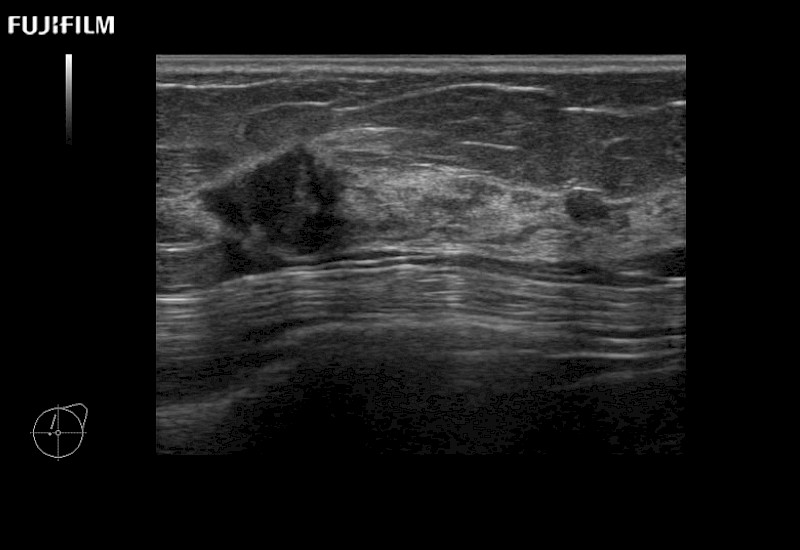

for use during open and laparoscopic procedures: Tumor localization & staging, Ablation, Resection, Biopsy, Transplant, Abdominal exploration, Robotic surgery

The ARIETTA 650 DI combines trusted Fujifilm Healthcare technologies and features tailored for surgical oncology.

Designed to meet the demands of surgeons, the ARIETTA 650 DI offers precise guidance. Its advanced capabilities and large, intuitive display offer accurate and efficient care in operating rooms and specialized surgical settings.

Learn moreFujifilm Healthcare continues to listen to the experts, our neurosurgeons, by developing an ultrasound system specifically designed for the Operating Room.

Guidance is the fundamental purpose for all of our surgical ultrasound technology. Fujifilm Healthcare is committed to designing tools that help neurosurgeons navigate inside the human body and provide the necessary information to immediately make critical surgical decisions.